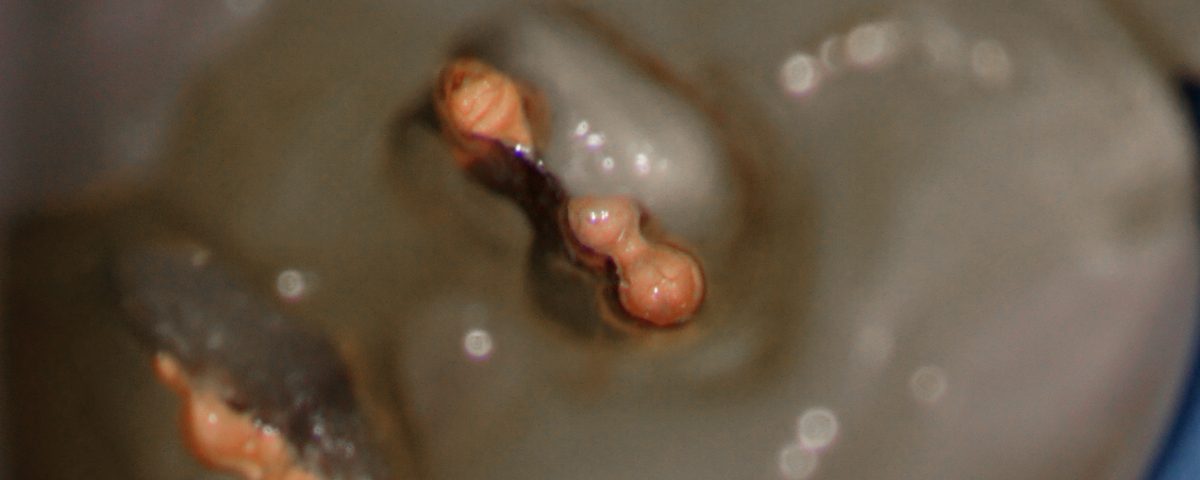

#19 Caries Driven access

Clinical Scenario and treatment done DO caries with a deep sub-gingival margin Resorbed apex – Distal root (H/O Orthodontic treatment) Surprisingly had a good tug-back all the way in the distal canals Shaped to 4% 30 Distal and 4% 25 in the mesials Obturation technique – WVC